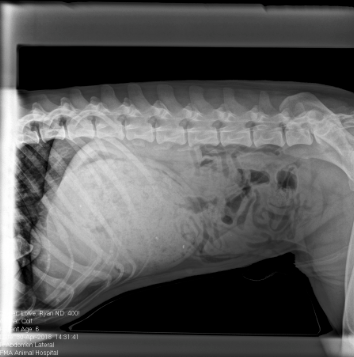

Obstructions. They usually occur 5 minutes before closing or when a new staff member drops the Q word. But what happens when the x ray isn't telling you the truth... or is it?

The following pets consumed items which are deemed medically impossible, yet they defied the odds and lived to tell the tale.

Can you guess just by looking at the x rays what each pet ate while their owners were oblivious? The results just might surprise you......